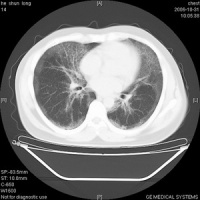

肺泡蛋白沉积症(pulmonary alveolar proteinosis'pap)是一种罕见的肺部疾病,病因不明,临床表现以活动后气促、咳嗽、咳少量白色黏液痰为主,无特征性,极易误诊[1],诊断主要依赖于病理学检查。多层ct(msct)的问世,使单次屏气时间内完成高质量的全肺薄层扫描成为现实,极大提高了图像的时间和空间分辨率,胸部高分辨率ct(hrct)还能清晰显示次级肺小叶为单位的肺内细微结构,极大提高了ct在肺部疾病诊断中的应用价值。本文收集经病理证实的6例pap,综合国内外有关文献 ,探讨pap的影像病理学联系及其多层ct表现特征,旨在提高对本病的认识和诊断。

本组共6例经病理学证实为pap患者,其多层ct诊断结果分别为:特发性肺间质纤维化2例;浸润型肺结核1例;肺泡癌1例;肺炎1例;肺泡蛋白沉积症1 例,诊断正确率17%。6例患者均见双肺散在分布的毛玻璃样高密度影,密度欠均匀,形态呈三角形、方形和多边形,少数呈圆形、弧形或线形,全部病灶边界清楚。其中4例可见部分病灶融合呈片块状。所有患者病变分布以肺门区及肺野外带为主,上下肺叶均可见到,在周围正常肺组织衬托下。4例患者的hrct图像还可见到在斑片状毛玻璃影中增多、增粗、紊乱的肺小叶间隔,呈铺路石样(crazy paving appearance)表现[4'5],见图2。病变与周围肺组织分界清楚,相邻肺组织未见明显异常表现。本组所有病例未见支气管气像,msct增强扫描均未见病灶强化以及纵隔肺门淋巴结肿大征象。心脏大小形态在正常范围。

肺泡蛋白沉积症临床非常罕见,由rosen等[6]于1958年首先报道,其病因及发病机制至今仍不清楚, 目前认为与肺泡表面物质代谢异常或肺泡巨噬细胞的清除异常有关,部分患者还可能与粉尘或某些化学物质吸入所致的特异性反应有关,也可能与自身免疫机制障碍、血液淋巴系恶性肿瘤以及细胞毒性药物的应用有关3.1 影像与病 理学 联系 肺泡腔内充满大量粉红色云絮状或细颗粒状无定形蛋白质样物质为pap的主要病理改变,而肺泡壁、支气管壁和胸膜病变不明显。病变区与相邻正常肺组织界限清楚,肺泡结构保持完整,肺泡间隔多数正常,少数可因间隔水肿及淋巴细胞浸润而增厚[8]。病变 发展的不同阶段,肺泡蛋白沉积症出现不同的影像学征象。当病变仅累及肺泡腔,以蛋白质样物质充填肺泡腔为主,而肺泡间隔无水肿及炎症细胞渗出时,ct检查可见肺野内毛玻璃样斑片状高密度影,病变与周围正常肺组织形成明显分界,在肺野中呈地址样表现[2'3]。本组所有患者均可见此征象。其形成机制尚不明确,可能与病变分布以肺小叶为单位,小叶间隔在一定程度上限制了病变蔓延有关。根据 文献,即使做过肺灌洗的患者,其剩余的肺实变仍然边界清楚[5]。msct增强扫描病灶未见强化,说明病灶缺乏血供及无肉芽组织形成。当病变累及小叶间隔,小叶间隔因水肿及炎症细胞浸润而增厚时,hrct上可见实变区出现增厚的小叶间隔,围绕实变的肺小叶形成铺路石样表现,具有一定的特征性[4'5]。本组4 例患者见此征象。hrct能够清楚地显示pap患者的次级肺小叶结构,发现胸部x线平片及常规ct所不能发现的pap患者肺小叶及小叶间隔病变,从而更好地评定病变范围及严重程度,具有重要价值。本组中hrct图像显示pap患者增粗的肺纹理符合小叶间隔走行,与肺部纤维化表现不同,病理学上pap患者的小叶间隔也无纤维化改变发生。pap病变分布以双肺多见,可仅累及一侧[9],肺野中央及外周均可发生,上下肺分布无明显差异[3'9'10]。文献报道当实变肺泡与含气肺泡混杂并存时,还可见到实变阴影内出现蜂窝状透光区,但是支气管气像不多见[9]。本组病例中均未见。肺泡蛋白沉积症为非感染病变,部分学者认为该病不伴有纵隔、肺门淋巴结肿大,若出现明显淋巴结肿大则多数与感染有关[11]。本组所有病例均未见到纵隔、肺门淋巴结肿大。

总之,对于肺部弥漫性病变,ct表现为地址样及铺路石样时,高度提示pap诊断。胸部ct扫描特别是hrct能提高对pap的早期正确诊断。[4'7'8]。本病好发于30~50岁成人,偶见于儿童及老年患者,男性多于女性。多数患者起病隐袭,临床表现无特征性,常见症状为活动后气促、咳嗽、咳少量白色黏液痰,亦可为干咳无痰。低热、乏力、胸痛、咯血者少见,部分病例可咯出小块胶冻样物质。部分患者体格检查可闻及少许肺底部湿啰音,约1/5患者出现杵状指,重者可致发绀。患者预后差异大,部分可自行缓解,复发常见,约1/3患者因呼吸衰竭或合并感染而死亡。